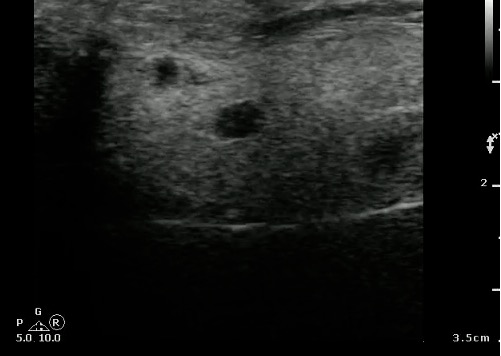

- Figure 19 and 20. Parotid gland lymph nodes

- The Parotid gland has intraglandular lymph nodes that are commonly seen within the parenchyma of the parotid gland.